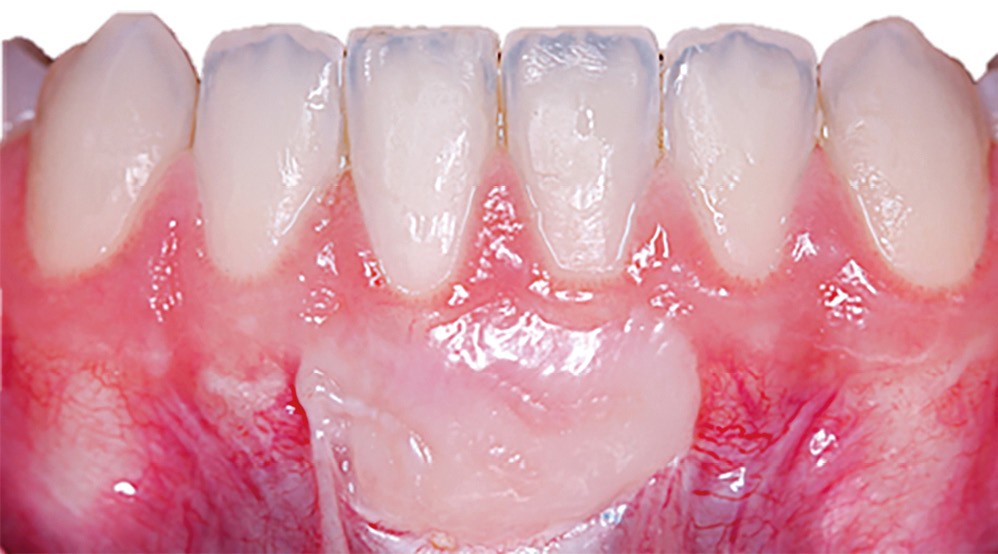

Les greffes de tissu conjonctif consistent en l’insertion d’un greffon de tissu conjonctif prélevé dans la cavité buccale, sous un lambeau déplacé (avec ou sans décharges), une enveloppe ou un tunnel. C’est la technique de choix pour le recouvrement radiculaire [13], que ce soit pour des récessions unitaires ou multiples, mais elle est aussi indiquée dans l’augmentation en épaisseur des parodontes fins avant traitements prothétiques, orthodontiques ou implantaires.

De nombreuses techniques de lambeaux déplacés latéralement, lambeaux déplacés coronairement (fig. 4), enveloppes ou tunnels (fig. 5) ont fait l’objet de publications et présentent des résultats quasi identiques en termes de recouvrement. Leurs points communs sont un recouvrement complet du greffon, une dissection en épaisseur partielle suffisante pour assurer un positionnement du lambeau sans tension et l’absence (quand cela est possible) d’incision de décharge. Le choix d’une ou l’autre technique dépend surtout de l’expérience du praticien et de la quantité de tissu disponible apicalement ou latéralement.